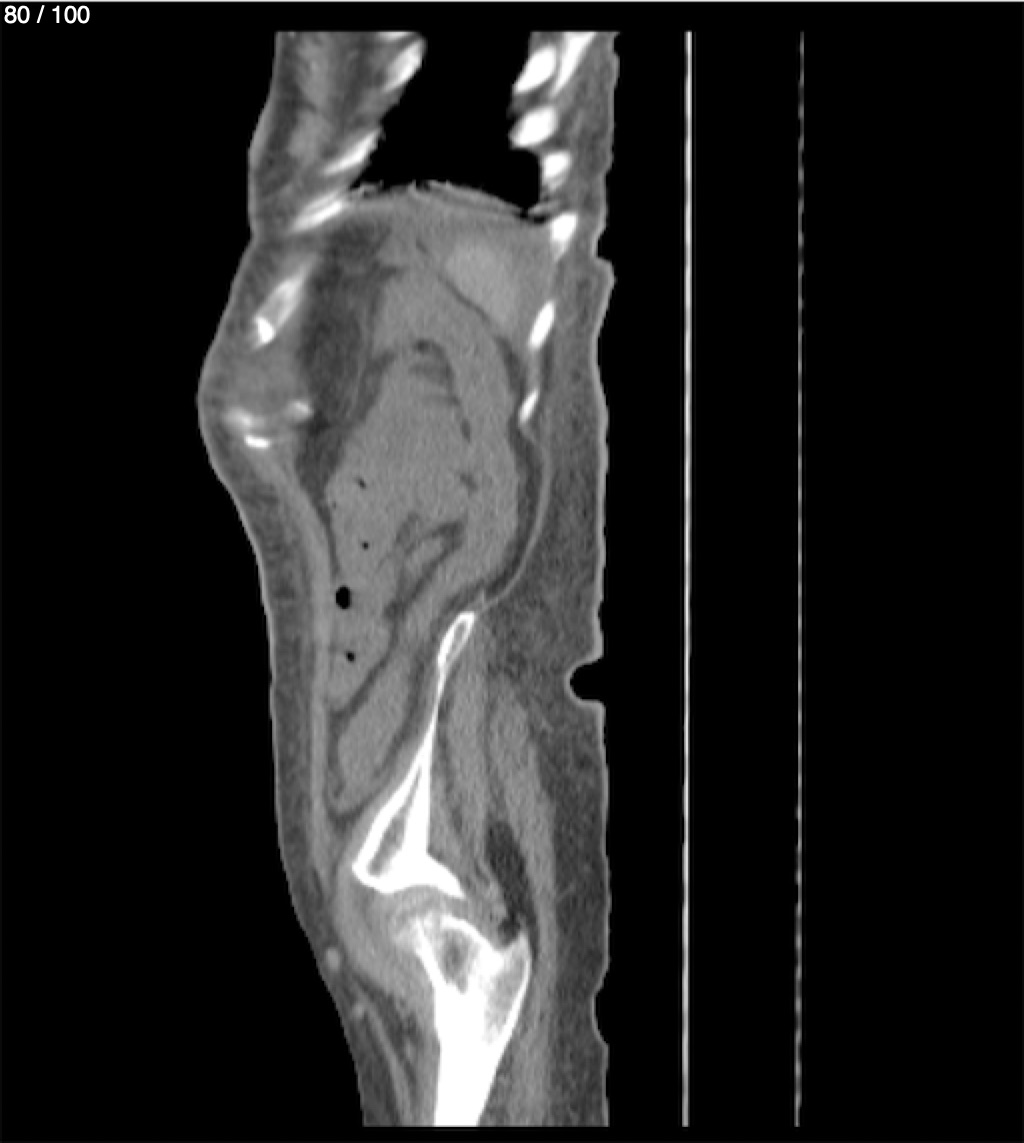

Hilda Geronimo Mendez 60A - T.C Abdomen Simple